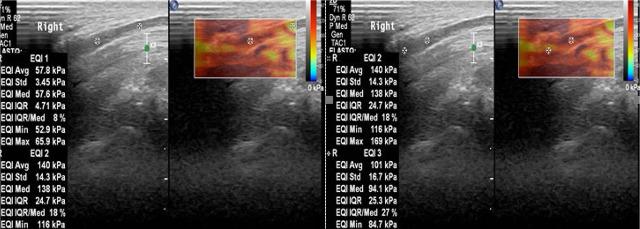

A prospective case-control study was conducted on 50 participants (50 wrists), including 25 carpal tunnel syndrome cases diagnosed by nerve conduction study and 25 healthy controls. Shear wave elastography assessed the stiffness of the median nerve at three locations: outside the carpal tunnel, at the inlet, and at the outlet. Cross-sectional area measurements were also obtained using B-mode ultrasound. Receiver operating characteristic curves were used to evaluate diagnostic performance.

Shear wave elastography and cross-sectional area demonstrated high diagnostic accuracy for carpal tunnel syndrome, with a cut-off value of ≥63.5 kPa inside the tunnel (mean of inlet and outlet values) and a cross-sectional area cut-off of ≥0.08 cm at the inlet of the tunnel offering optimal performance. While cross-sectional area provided high sensitivity, shear wave elastography showed superior specificity; their combination improved overall diagnostic accuracy. Shear wave elastography values did not significantly differ across carpal tunnel syndrome severity grades based on nerve conduction study ( >0.05). However, shear wave elastography at the tunnel inlet differentiated severe carpal tunnel syndrome from non-severe cases ( = 0.045), with a cut-off of ≥126 kPa predicting severe carpal tunnel syndrome with 100% sensitivity, 77% specificity, and an area under the receiver operating characteristic curve of 0.871.

剪切波弹性成像和横截面积对腕管综合征具有较高的诊断准确性,隧道内(入口和出口值的平均值)的截断值≥63.5kPa,隧道入口处的横截面积截断值≥0.08cm²时表现最佳。虽然横截面积具有较高的敏感性,但剪切波弹性成像显示出更高的特异性;两者结合提高了整体诊断准确性。基于神经传导研究,不同严重程度等级的腕管综合征患者的剪切波弹性成像值无显著差异(P>0.05)。然而,隧道入口处的剪切波弹性成像可区分重度腕管综合征与非重度病例(P = 0.045),截断值≥126kPa预测重度腕管综合征的敏感性为100%,特异性为77%,受试者工作特征曲线下面积为0.871。